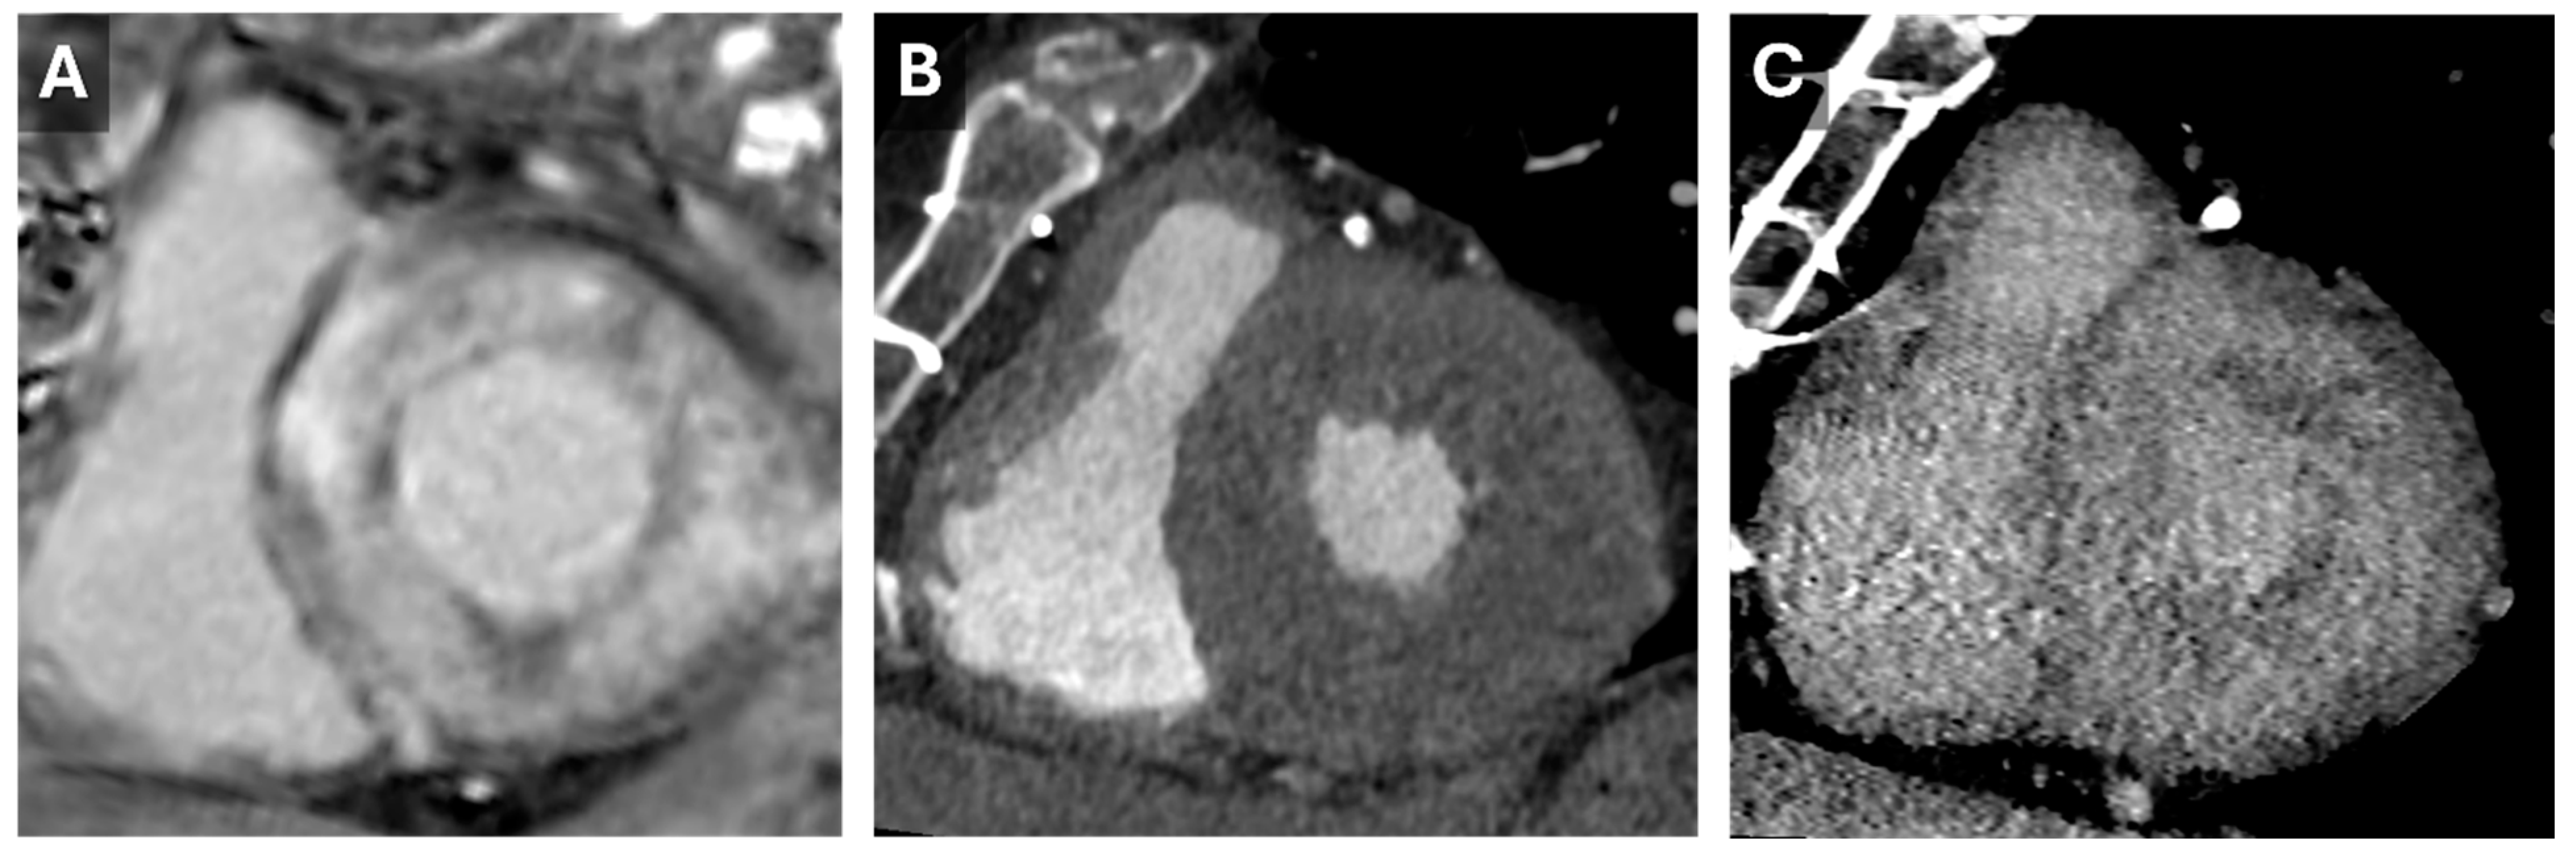

8. Cardiac Ablation Pre-Procedural Planning

- Conte, E.; Mushtaq, S.; Carbucicchio, C.; Piperno, G.; Catto, V.; Mancini, M.E.; Formenti, A.; Annoni, A.; Guglielmo, M.; Baggiano, A.; et al. State of the art paper: Cardiovascular CT for planning ventricular tachycardia ablation procedures. J. Cardiovasc. Comput. Tomogr. 2021, 15, 394–402. [Google Scholar] [CrossRef]

- Muser, D.; Nucifora, G.; Castro, S.A.; Enriquez, A.; Chahal, C.A.A.; Magnani, S.; Kumareswaran, R.; Arkles, J.; Supple, G.; Schaller, R.; et al. Myocardial Substrate Characterization by CMR T1 Mapping in Patients With NICM and No LGE Undergoing Catheter Ablation of VT. JACC Clin. Electrophysiol. 2021, 7, 831–840. [Google Scholar] [CrossRef]